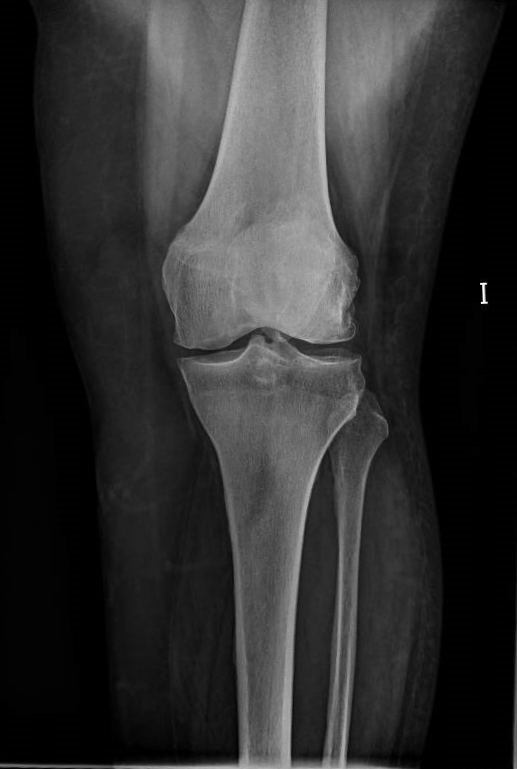

Diagnostico

Los estudios previos para el diagnostico de una artrosis de rodilla son principalmente un examen clínico del médico y las radiografías. El examen medico habitualmente confirma dolor en la parte medial, anterior y lateral de rodilla, rigidez con reducción en el rango de movimiento, crepitación o roce con el movimiento de la rodilla y cojera durante la marcha. En la radiografía típicamente se observa los cambios en la forma del hueso y cartílago como la pérdida de grosor, deformación y endurecimiento. Ocasionalmente para confirmar el diagnóstico de la patología de un compartimiento o de una fase muy inicial, se puede usar otras pruebas de imagen como la resonancia magnética, tomografía computarizada (TC) o gammagrafía ósea que valora mejor las partes blandas alrededor de la articulación.